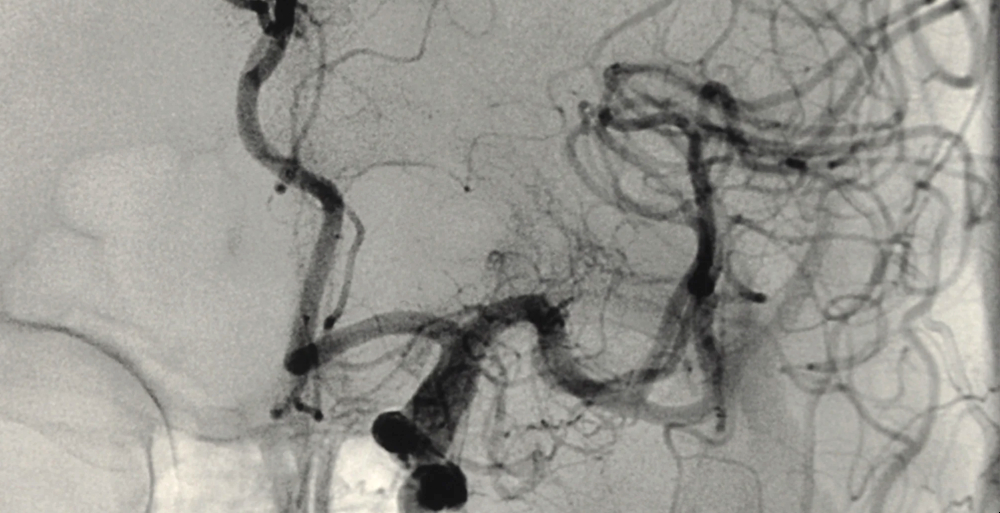

Diagnozo potrdijo z biopsijo prizadete krvne žile. Včasih je potrebna tudi biopsija jeter ali ledvic. Z arteriografijo lahko odkrijejo žilne okvare. Brez zdravljenja preživi 1 leto le 33 odstotkov bolnikov, 88 odstotkov jih umre v 5 letih. Z agresivnim zdravljenjem je smrt mogoče preprečiti.

Slika: Z arteriografijo lahko odkrijejo žilne okvare.